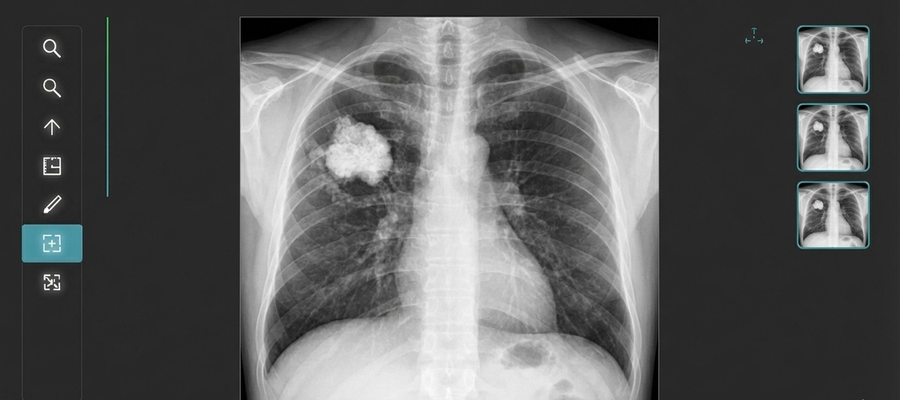

Yes, X-rays can sometimes reveal signs of bone cancer. However, they do not directly “see” cancer cells. Instead, they show structural changes in the bone that may suggest a tumor.

If bone cancer is present, an X-ray may reveal:

- Areas of bone destruction (osteolytic lesions)

- Abnormal bone growth (osteoblastic lesions)

- Irregular bone shape or structure

- Bone thinning or weakening

- Unexplained fractures

- Soft tissue swelling near the bone

These changes raise suspicion, but they do not confirm cancer. Further testing is almost always required.

What Does Bone Cancer Look Like on an X-Ray?

Radiologists are trained to look for specific patterns. Some common appearances include:

- “Moth-eaten” bone destruction

- Periosteal reaction (new bone forming around a lesion)

- Sunburst pattern (spiculated bone growth)

- Codman triangle (elevation of periosteum)

- Mixed lytic and sclerotic areas

These patterns do not automatically mean cancer, but they guide further investigation.